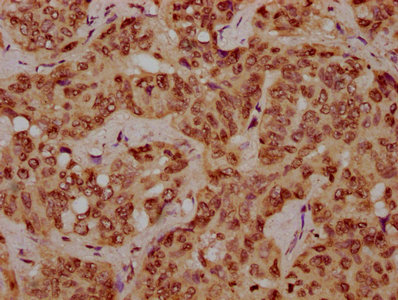

IHC image of CSB-PA010378OA116nhibHU diluted at 1:10 and staining in paraffin-embedded human liver cancer performed on a Leica BondTM system. After dewaxing and hydration, antigen retrieval was mediated by high pressure in a citrate buffer (pH 6.0). Section was blocked with 10% normal goat serum 30min at RT. Then primary antibody (1% BSA) was incubated at 4°C overnight. The primary is detected by a biotinylated secondary antibody and visualized using an HRP conjugated SP system.